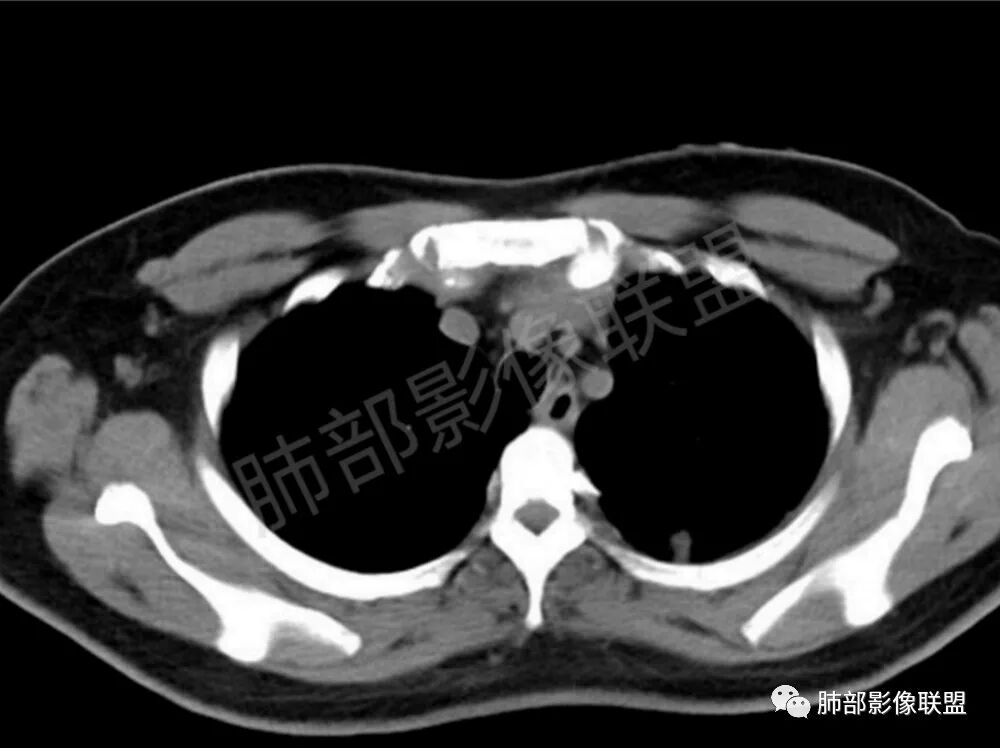

两肺多发结节性,大部分位于胸膜下,部分结节周围可见晕征。局部结节内可见扩张的支气管,纵隔淋巴结大,脾大,22岁男,HIV阳性,常规先考虑隐球菌。鉴别淋巴瘤,结核,马儿。

男,22,半年前咳嗽伴少痰,查HIV阳性,痰查TB阳性,既往有肺部斑片影伴空洞、纵隔淋巴结肿大、脾大。SCC、CA50、CA199、FER增高,此次胸部CT:两肺多发结节影,部分沿血管束分布,部分贴胸膜下,大小不一,密度不一,部分较散、边缘模糊,部分较实、圆钝、周围模糊晕,部分结节有支气管进入穿行自然,部分结节有血管分支自如通过。考虑HI∨相关淋巴增殖类病变,淋巴瘤?LYG?鉴别PC、TB。

青年男性,半年前咳嗽,HIV阳性,结核DNA阳性,肿标糖类抗原和铁蛋白增高。外院影像有纵隔淋巴结增大伴脾大,肺部病灶空洞。现在影像:肺内多发沿支气管分布(有支气管充气征,长轴沿支气管分布)及胸膜下分布(平行于胸膜)的大小不等结节,个别伴有空洞,双侧腋窝淋巴结肿大。纵隔图片不够,是否还有淋巴结肿大未知,脾脏未显示。

1、HIV相关淋巴瘤,有HIV阳性,有纵隔及腋窝淋巴结肿大,肺内病灶沿支气管分布(中轴淋巴间质)及胸膜下分布(周围淋巴间质),有脾大,这个是必须要考虑的。但是原来的影像是肺斑片影伴空洞,又有疑问,需要穿刺明确。

影像学缺乏特征性,以支气管血管周围、胸膜下及双肺下叶周边多发结节影最多见,结节易坏死形成空洞,伴有游走性和多变性的特征,结节周围可有磨玻璃样晕征,有时也可见单发结节影、薄壁的囊状阴影或弥漫性浸润影。肺门、纵隔淋巴结肿大少见, 可见胸腔积液和气胸。